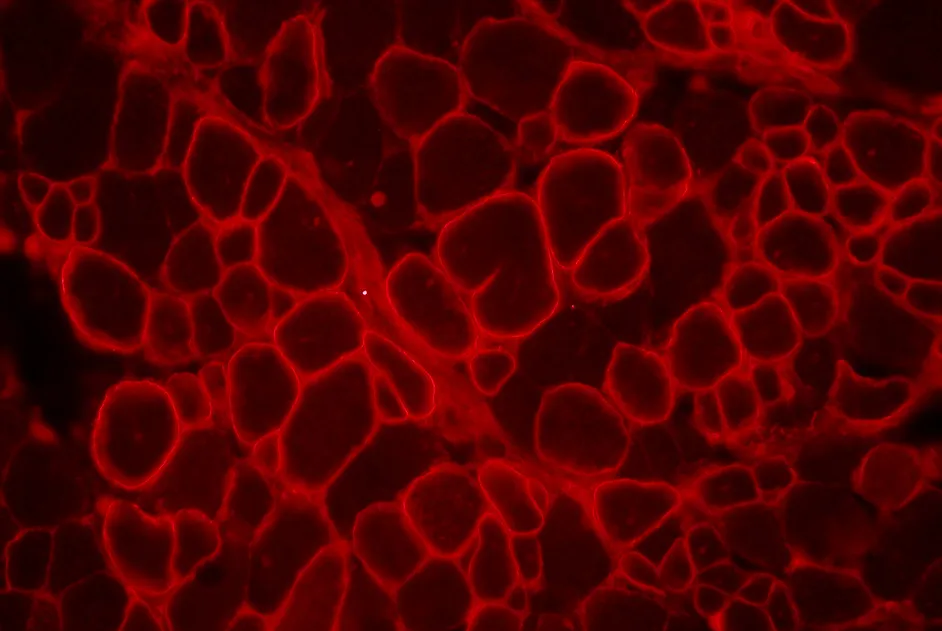

Les anomalies du gène DYSF, responsables de la myopathie des ceintures de type 2B (LGMD2B), aboutissent à la production d’une dysferline mal repliée, qui, au lieu de s’intégrer à la membrane cellulaire, va constituer des agrégats à l'intérieur de la cellule, dans le réticulum endoplasmique.

Une équipe allemande a montré dans un article publié en novembre 2012 que des peptides dérivés de la dysferline sont capables de pénétrer dans le réticulum endoplasmique, d’en réduire le stress et d’y interférer avec les agrégats de dysferline dépliée permettant à la protéine anormale de se relocaliser dans la membrane. En retrouvant sa position transmembranaire, la protéine anormale redevient fonctionnelle.